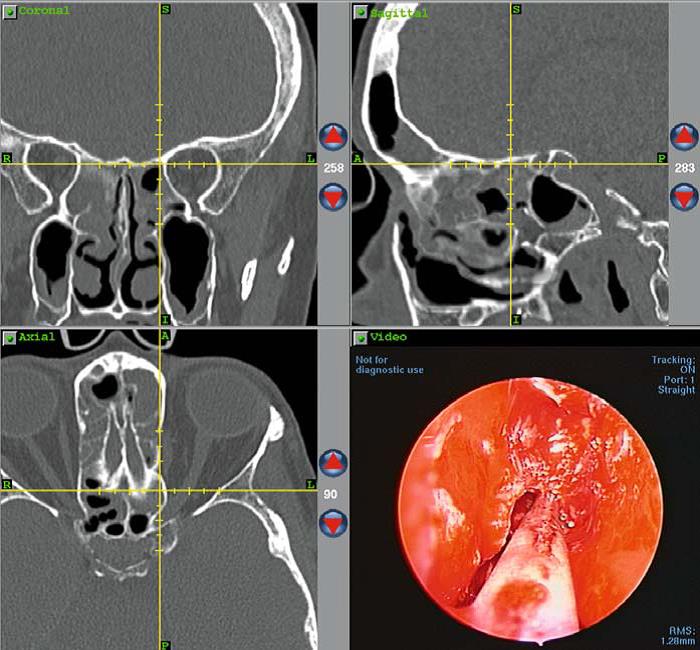

Máy định vị thường dùng hiện nay là loại không khung, không dây. Bệnh nhân sẽ được chụp cắt lớp vinh tính đa lát cắt, các dữ liệu sẽ được chuyển cho máy tính của hệ thống. Độ chính xác 2mm là được chấp nhận cho phẫu thuật và các dụng cụ phẫu thuật định vị. Hình ảnh cắt đứng, ngang và dọc của xoang sẽ được hiển thị trên nàn hình ở vị trị đầu dò. Do vậy hệ thống máy định vị sẽ định vị, cho biết được cùng một lúc vị trí của đầu thăm dò, trên 3 bình diện trên màn hình hiển thị.

Với hệ thống này phẫu thuật viên gần như có thể đánh giá và phẫu thuật trên không gian 3 chiều.